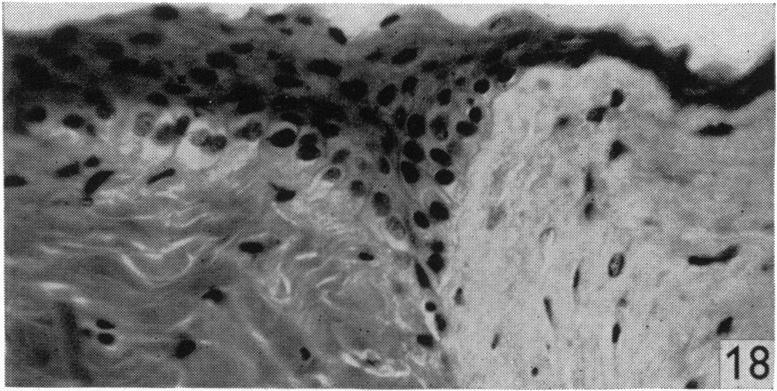

A note on the specificity of the corneal epithelium.

J Anat. 1950 Jan;84(Pt 1):50-6.